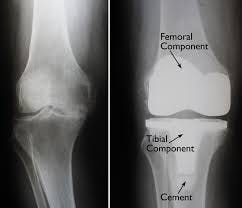

In addition to his expertise in hand surgery, Dr. Agarwal is a leading joint replacement surgeon in Jaipur. He offers cutting-edge treatments for patients with arthritis or joint degeneration, including knee replacement surgery. Using advanced techniques, Dr. Agarwal helps patients regain mobility and improve their quality of life. His comprehensive approach includes both partial and total knee replacement options, tailored to the patient’s needs.